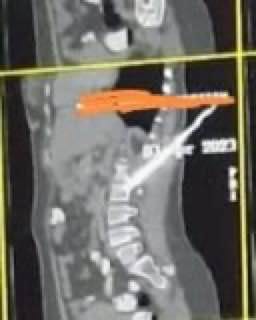

نجح فريق طبي من مستشفى الطوارئ والاستقبال بقصر العيني بـ جامعة القاهرة، في إجراء عملية جراحية حرجة لاستخراج سكين من ظهر سيدة تم طعنها به، واستغرقت العملية الجراحية 3 ساعات فقط، بما يمثل إضافة جديدة إلى سجل نجاحات مستشفيات قصر العيني المشهودة وتميُز كوادرها الطبية.

من جهتها، قالت الدكتور منال المصري عميدة كلية طب قصر العيني ورئيسة مجلس إدارة مستشفيات جامعة القاهرة، إن العملية الجراحية التي تم إجراؤها كانت على جانب كبير من الخطورة خوفًا من دخول السكين في أحد الشرايين الأساسية أو الحبل الشوكي أو الأمعاء.

وأضافت أنه تم عمل الإجراءات الطبية اللازمة بشكل سريع قبل إجراء الجراحة مثل الأشعة المقطعية، وحجز أكياس الدم والبلازما اللازمة، وتم إجراء العملية الجراحية بمهارة كبيرة أسفرت عن استقرار حالة المريضة.